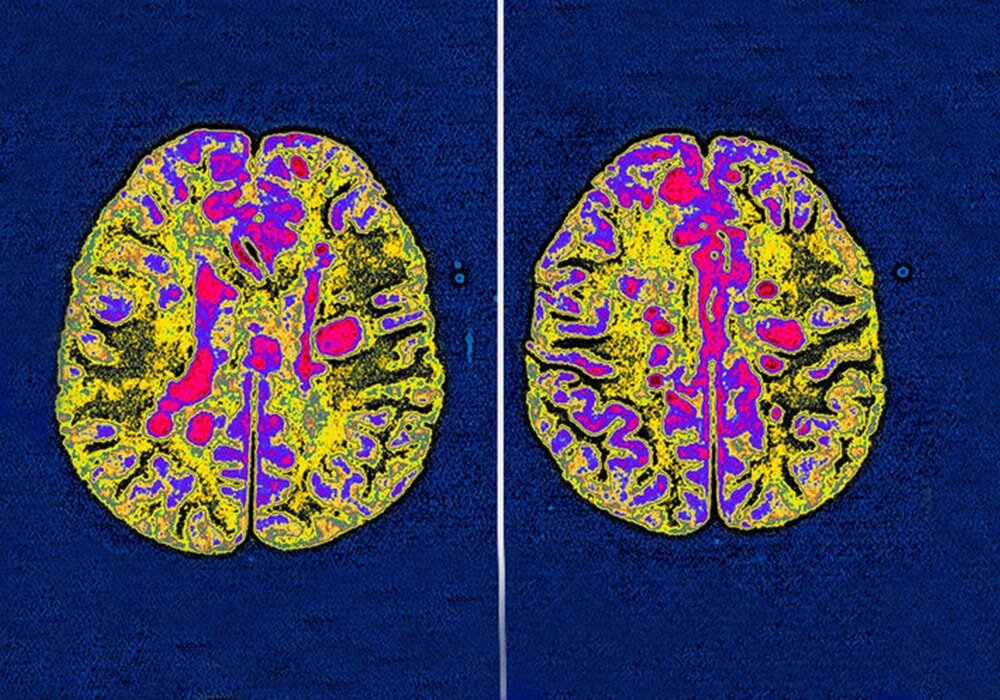

магнитно-резонансную томографию, которая помогает уточнить наличие и уровень поражения белого вещества; и спинномозговую пункцию с исследованием спинномозговой жидкости – ликвора.